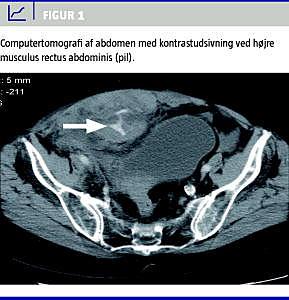

En 75-årig kvinde blev indlagt på grund af smerter i højre side af abdomen igennem to uger. Ved indlæggelsen var blodtrykket 100/75 mmHg, og pulsen var 87. Patient havde atrieflimren, hvorfor der var ordineret oral antikoagulationsbehandling (warfarin). INR var forhøjet til 3,9. Der var ingen traumer i anamnesen. Hæmoglobinkoncentrationen faldt fra 6,7 til 4,1 mmol/l under indlæggelsen. Der var primært mistanke om abdominal aortaaneurismeruptur, og der blev givet blodtransfusion samt frosset plasma og væsketilskud. En computertomografi (CT) af abdomen viste kontrastudsivning ved højre musculus rectus abdominis (Figur 1 ). Da patienten var fortsat hæmodynamisk ustabil trods blodtransfusion, besluttede man at udføre embolisering af det blødende kar umiddelbart efter CT. Der blev foretaget selektiv/superselektiv angiografi af højre a. epigastrica inferior, hvorved der blev påvist ekstravasation af kontrast. Derefter blev der udført embolisering af den blødende arteriegren med anvendelse af mikrokateter og flere 2 mm og 3 mm mikro- coils , hvorved den blødende arterie blev okkluderet. Lokal hæmostase i lysken var problemfri efter lukning af punkturen med StarClose (Abbott, USA). Derefter var patienten symptomfri med en gradvis hæmodynamisk stabilisering og ingen ny blødningsepisode.